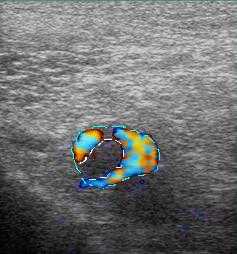

Повышения вязкости крови ведет к появлению эхогенности внутрисосудистого содержимого. Стенка у вен намного тоньше артериальной, и в норме всегда меньше 1 мм, не имеет деления на слои. Артериальная хорошо видна, дифференциация на слои отчетливая. При обследовании вен оценивают ее стенку, диаметр просвета, однородность просвета, внутрипросветные структуры, реакцию на функциональные пробы, как в черно-белом режиме, так и с цветовым кодированием кровотока. При проведении проб, на вдохе вены расширяются, работоспособные клапаны не пропускают кровь в противоположном направлении (от сердца к периферии), что отражается при цветовом кодировании кровотока как отсутствие цвета, в патологии же, цвет меняется на противоположный.

функциональных пробах и цветовом кодировании кровотока, когда в норме цвет исчезает, а при

несостоятельности клапана он меняется на противоположный.